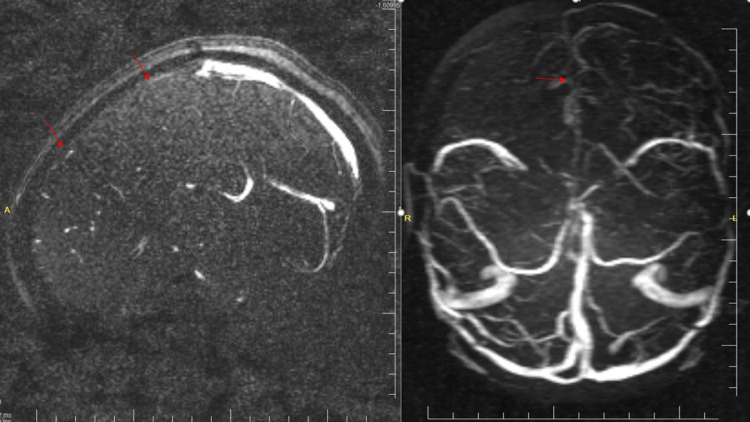

Case presentation: A 26-year-old farmer male presented with a snake bite and soon developed neurological complications, including diplopia, seizures, and altered mental status with Glasgow coma scale(GCS) of 11 out of 15. Investigations revealed coagulation abnormalities and magnetic resonance venography showed acute thrombosis of the superior sagittal sinus. The patient was diagnosed with superior sagittal sinus thrombosis. He was admitted to the intensive care unit and treated with anticoagulants to manage the thrombus, prevent further clot formation, and administer seizure medications to control any potential seizures associated with the condition. Moreover, we closely monitored the patient's condition to ensure effective treatment and to address any complications that may arise. Throughout the next three days, the patient's health gradually improved due to supportive care. He was extubated and transferred to the general ward. He was discharged after 10 days, having made a full recovery.